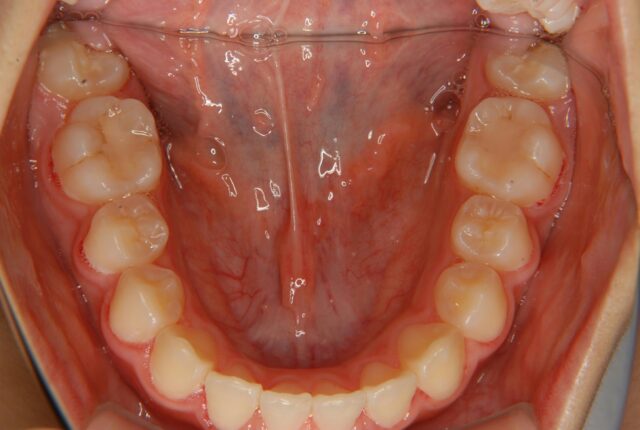

唇側矯正 小児矯正 反対咬合(受け口)の治療例【非抜歯】 この治療例は上下顎歯の唇側より矯正装置を装着して、反対咬合の改善を行った写真です。 治療前 治療後 主訴 受け口を治したい 診断名あるいは主な症状 下顎前突 年齢 10才 治療に用いた主な装置 唇側矯正装置 抜歯部位 非抜歯 治療期間 約2年 通院回数 24回 治療費概算 880,000円(税込) リスクと副作用 反対咬合を改善する時に上下の歯がぶつかり破折する可能性がある。下顎が後方に押し込まれ、顎関節に負担をかける可能性がある。